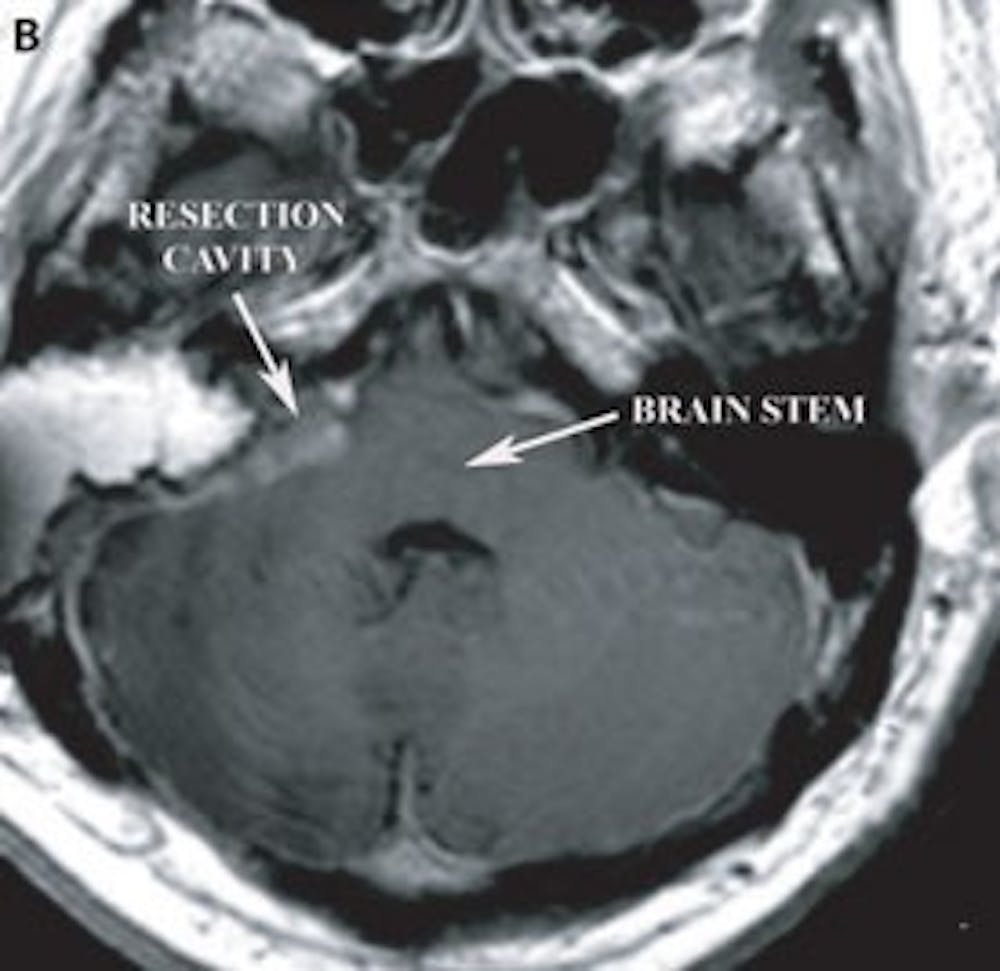

B) 術後軸向 T1 MRI 對比顯示手術切除腔和腦幹壓迫的消退